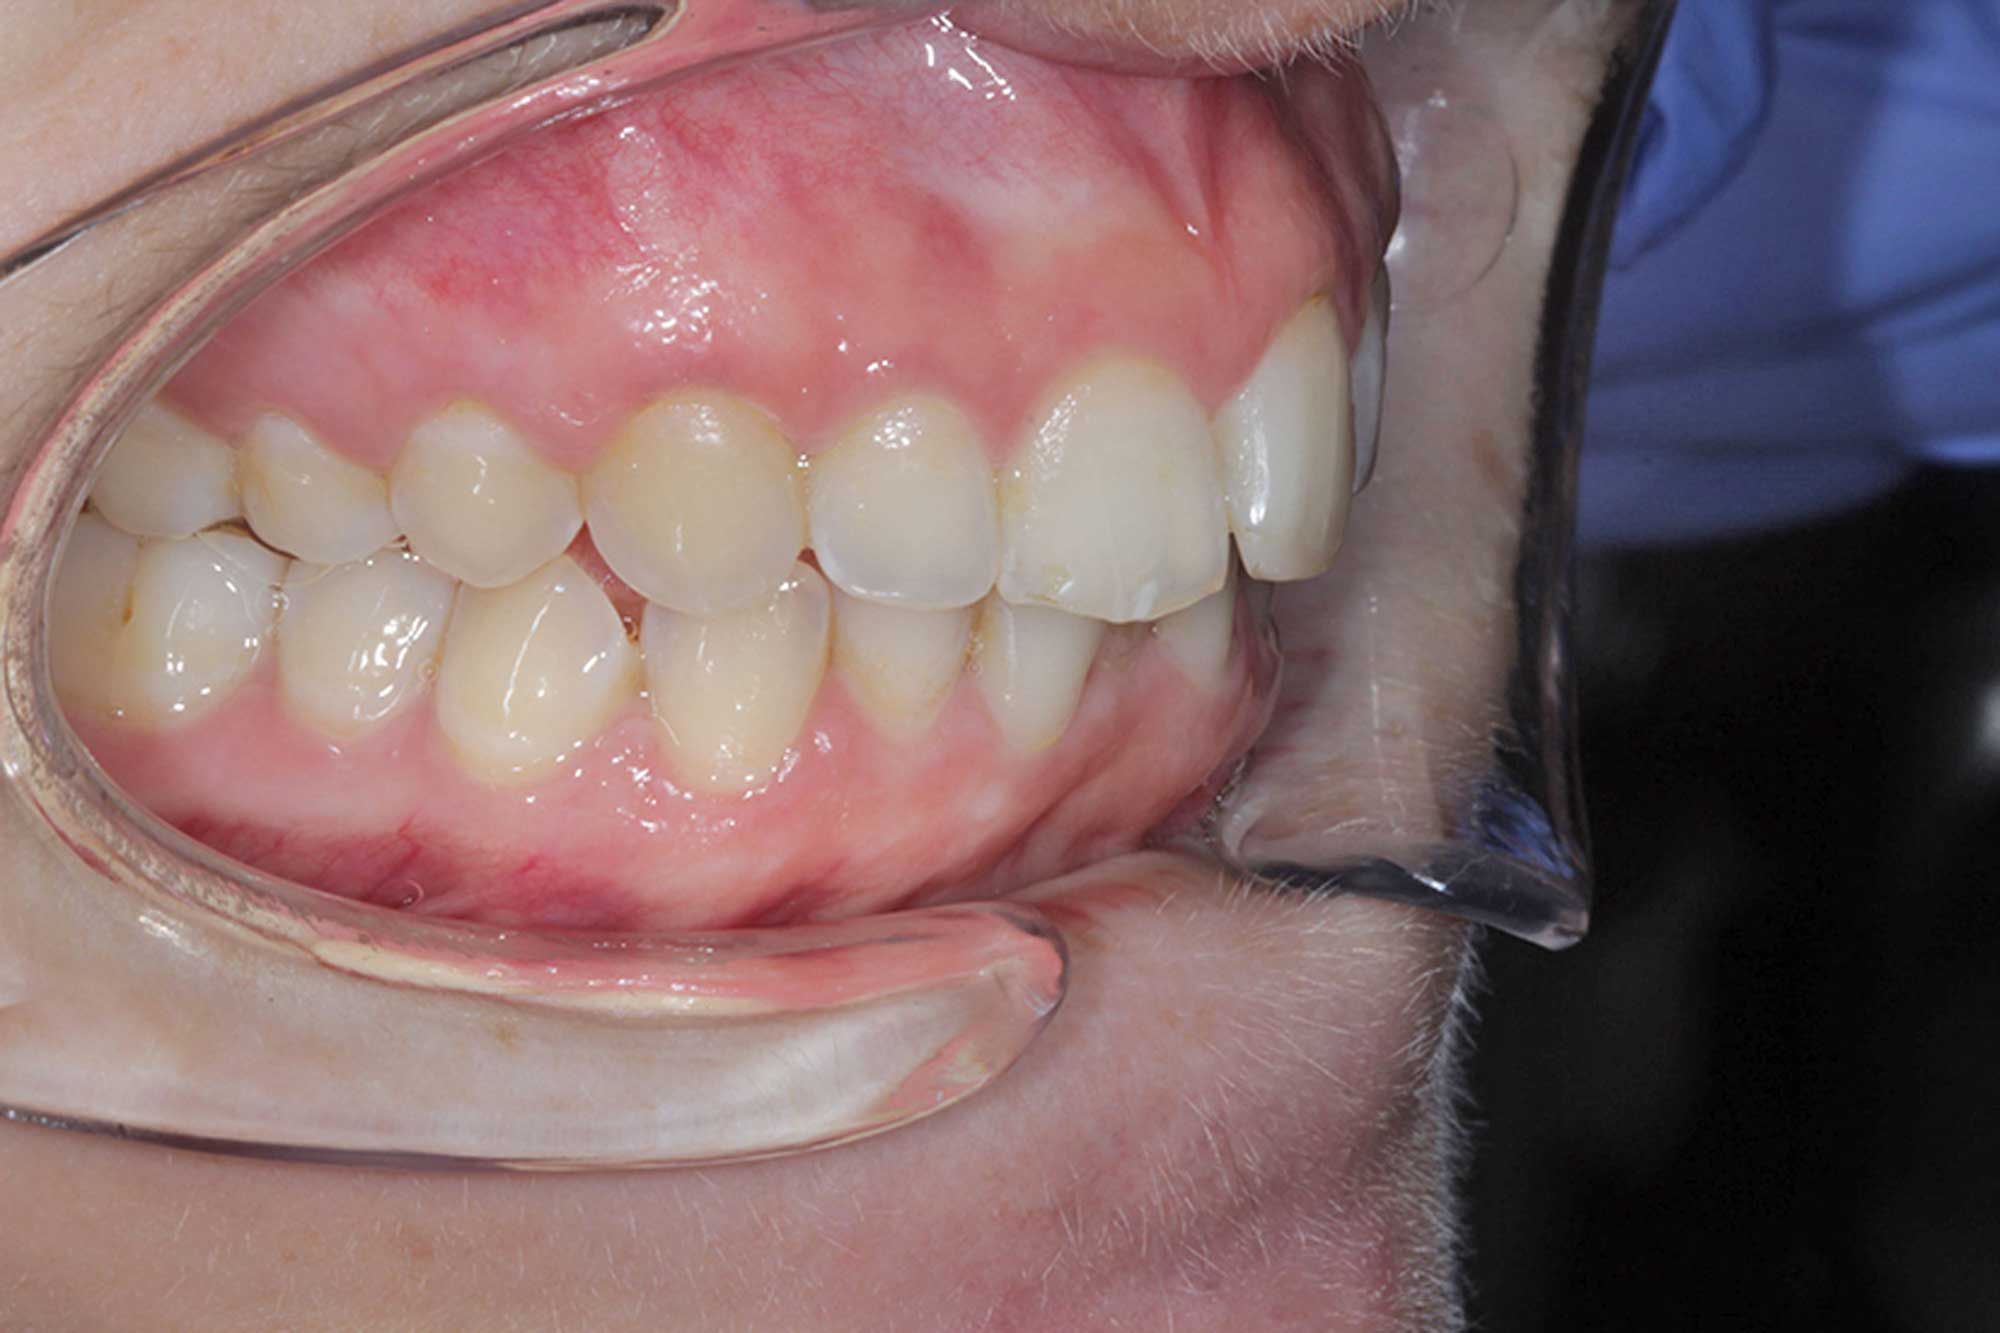

This young female patient presented with misalignment. She wanted a solution that would not only straighten her teeth but also give her the confidence in her smile she’d always wanted.

We started off with her aesthetic smile design, as we always do. She had beautiful smile proportions and the potential for perfection was certainly there as we concentrated on matching her gingival margins, widening her buccal corridors and accepting that incisal tooth wear had certainly taken place with some of the edges.

In this case, 14 aligners were needed to achieve the outcome we were looking for. This was followed by two short stages of refinements, as we certainly aimed for perfection in the end result and strived to match the original Clincheck prediction.